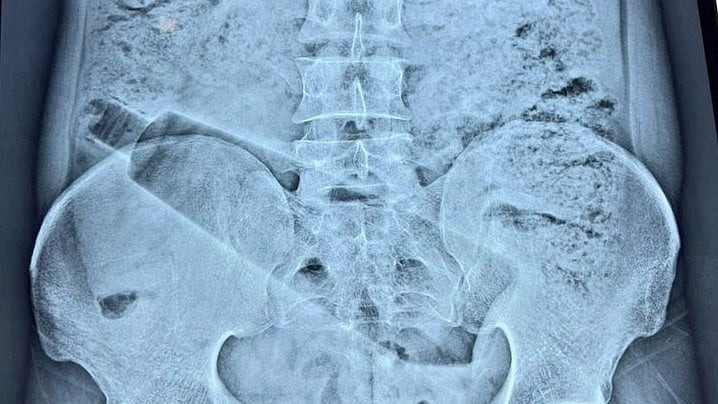

Qua kiểm tra lâm sàng và chụp X-quang, các bác sĩ phát hiện một chai nhựa dung tích khoảng một lít nằm bên trong trực tràng của bệnh nhân. Đây là tình huống được đánh giá có nguy cơ cao do khả năng gây tổn thương nghiêm trọng đến các cơ quan nội tạng.

Các bác sĩ phát hiện một chai nhựa dung tích khoảng một lít nằm bên trong trực tràng của bệnh nhân. Ảnh: Free Press Journal